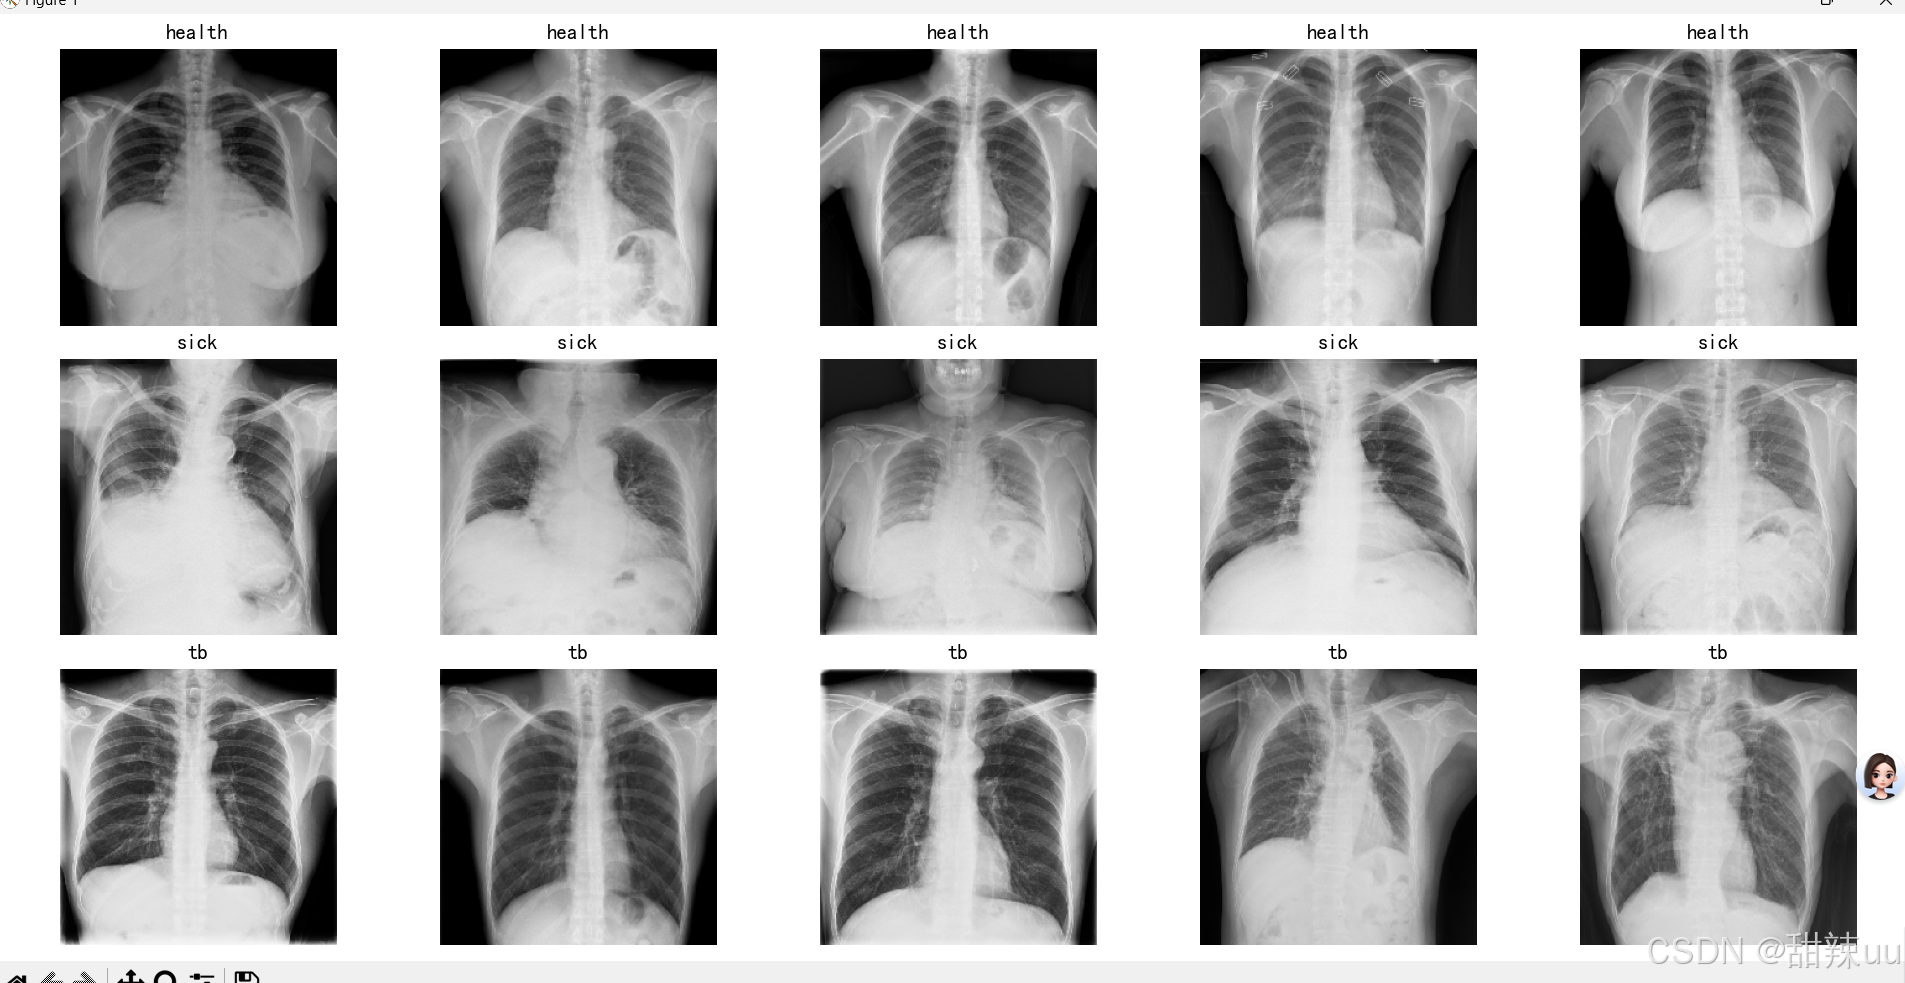

基于胸部X光片的肺炎诊断系统,是一款融合深度学习技术的医疗辅助工具,旨在解决临床胸部疾病诊断中效率低、依赖经验的痛点,尤其适用于基层医疗机构。 系统以CNN+Transformer混合模型为核心,通过多源胸部X光数据集训练优化,可精准识别肺炎、肺结核、肺癌三类常见肺部疾病。功能上支持PNG、JPG等格式图像上传与实时预览,上传后几秒内完成分析,输出诊断结果、置信度及三类疾病概率分布(可视化图表呈现),同时自动保存诊断记录,支持历史病例回溯、详情查看与删除,方便医护人员病例管理。 系统采用响应式设计,适配电脑、平板等设备,界面简洁直观,医护人员无需专业AI知识即可操作。经临床数据验证,模型诊断准确率达90%以上,可有效辅助医生减少漏诊、误诊,提升诊断效率,尤其为医疗资源有限地区提供技术支撑,助力基层肺部疾病早筛早诊。需注意,系统仅作辅助诊断,最终结果需结合医师临床判断。